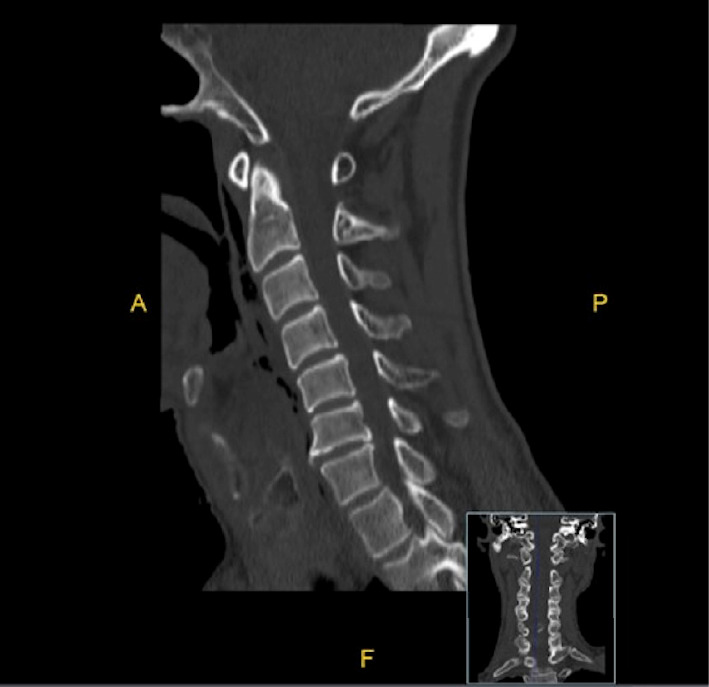

Introduction: Hypopharyngeal rupture caused by indirect neck trauma is a rare but potentially life-threatening injury. Delayed diagnosis can lead to severe complications, highlighting the importance of clinical suspicion and appropriate imaging. Case Presentation: A 64-year-old male patient sustained indirect neck trauma following a car accident. He was initially transferred to the hospital with mild symptoms and was discharged. However, a few hours later, he returned to the emergency department with neck pain, odynophagia, and dysphagia. CT imaging revealed evidence of hypopharyngeal rupture accompanied by retropharyngeal emphysema. The patient was managed conservatively with Nil Per Os (NPO), intravenous antibiotics, and the placement of a nasogastric (NG) tube. He achieved full recovery without complications. Conclusion: This case emphasizes the importance of thoroughly evaluating the relationship between clinical complaints and the mechanism of injury in patients with indirect neck trauma. High clinical suspicion, detailed history-taking, and appropriate imaging modalities are crucial for early diagnosis and effective management.